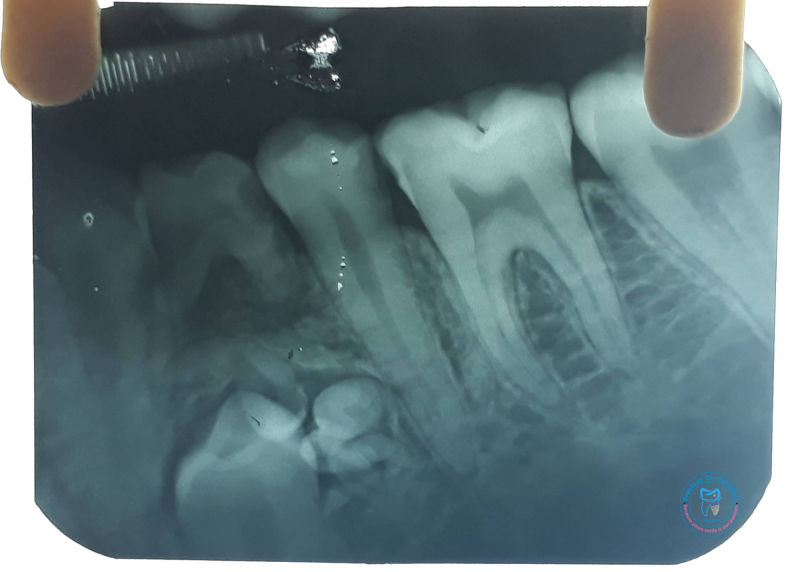

Root Carries AO with Canals